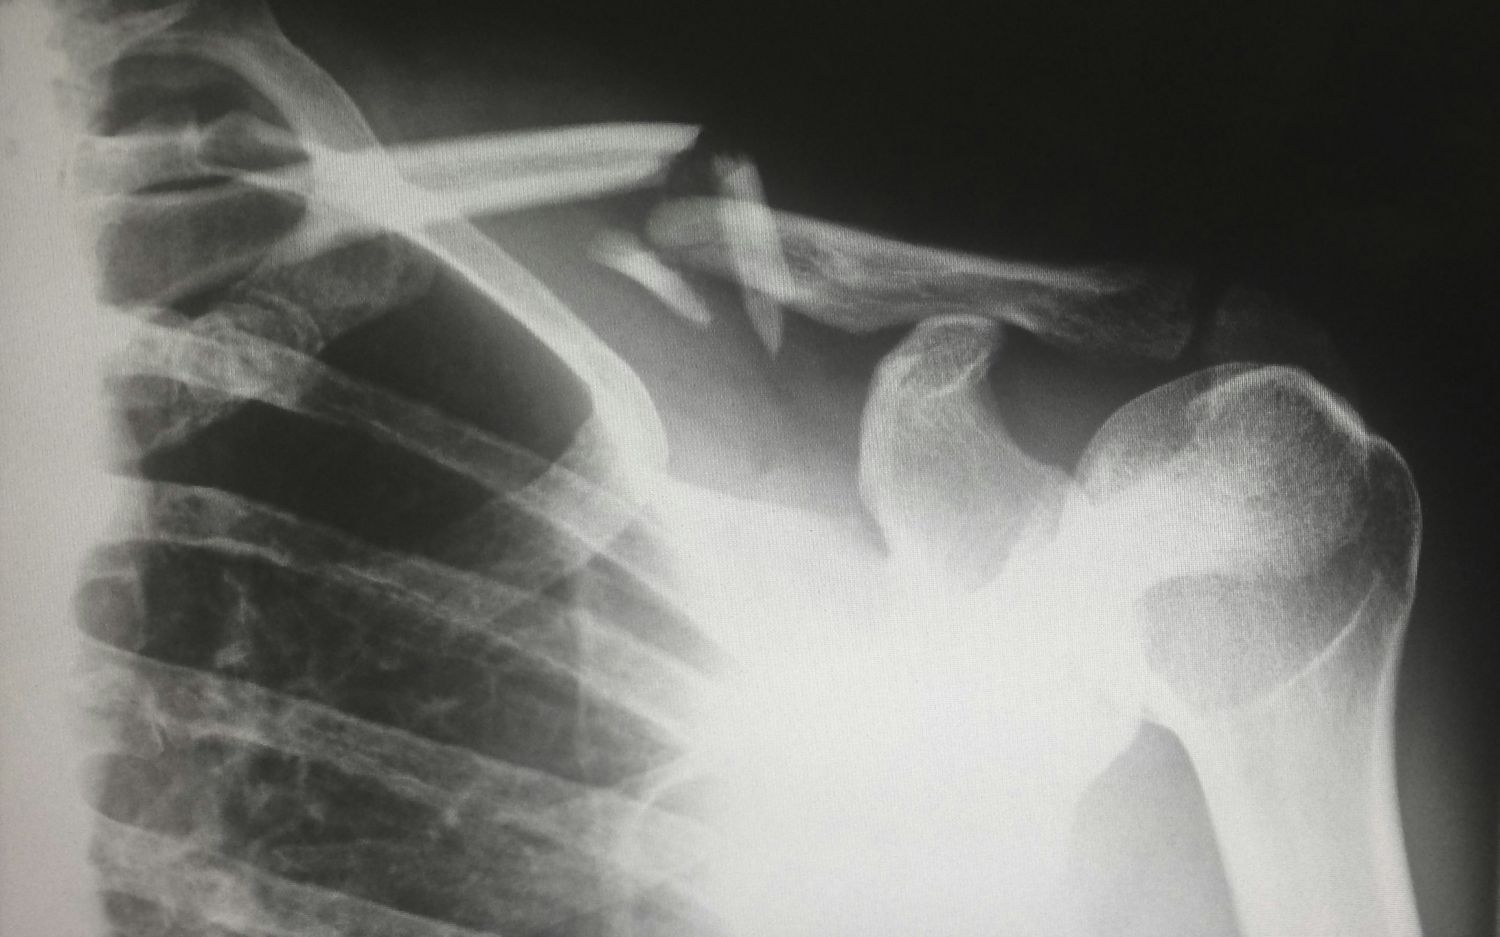

• Oberarm – oft Oberarmkopfbruch in der Nähe der Schulter

• Röntgenuntersuchung: Auf einem Röntgenbild sind Knochenbrüche jeglicher Art in der Regel gut erkennbar. Wir können den genauen Ort und das Ausmass der Fraktur sehen.